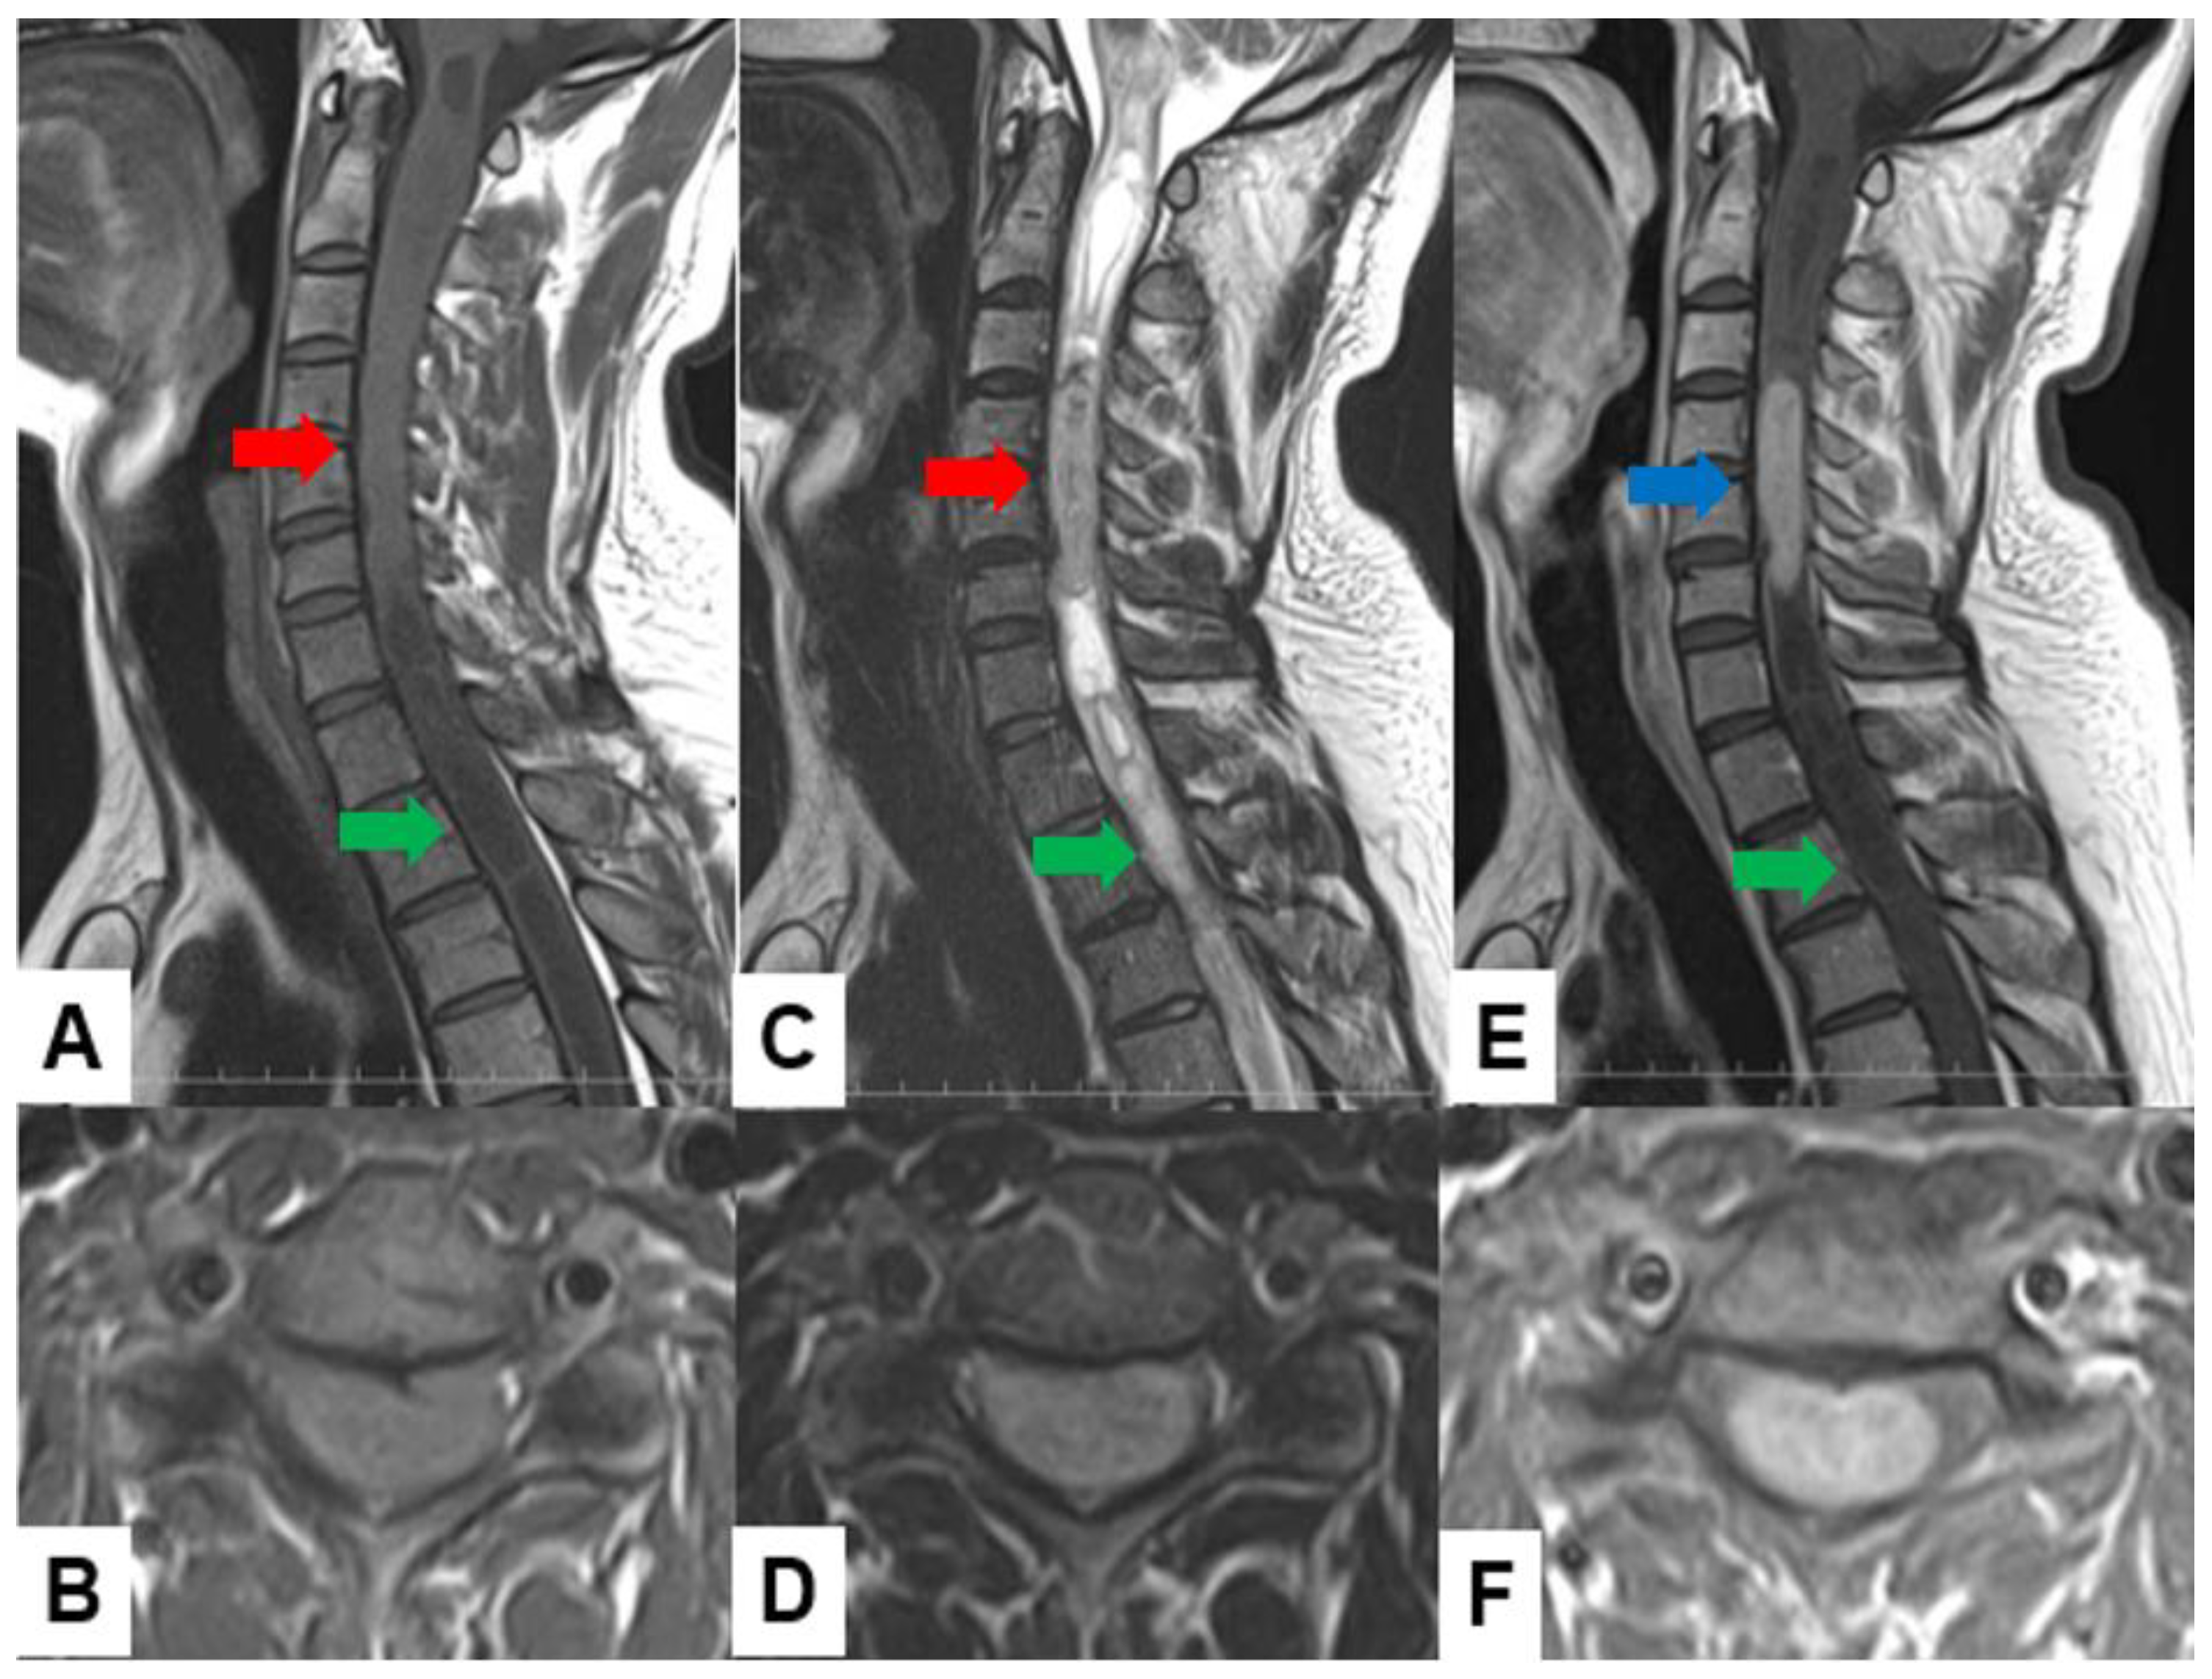

Astrocytoma: Pilocytic astrocytomas usually indicate well-circumscribed intramedullary masses with cystic lesions. These tumors exhibit a mixed signal intensity in both T1-weighted and T2-weighted images (Figure 5). High-grade astrocytomas, such as glioblastomas, present as infiltrative growth, with ill-defined margins and heterogeneous enhancement. These tumors may indicate surrounding edema.

Figure 5.

Fourteen M, spinal astrocytoma, grade 3. (A) T1-weighted midsagittal image, (B) T2-weighted midsagittal image, and (C) enhanced T1-weighted midsagittal image. Red arrows indicate tumor and blue arrow shows tumor enhancement.

Ependymoma: Myxopapillary ependymomas typically present as well-defined intradural extramedullary masses with a heterogeneous signal intensity in T1-weighted images and hyperintensity in T2-weighted images (Figure 6). These tumors often demonstrate avid contrast enhancement.

Figure 6.

Thirty-seven M, spinal ependymoma, grade 1. (A) T1-weighted midsagittal image, (B) T1-weighted axial image at C4/5, (C) T2-weighted midsagittal image, (D) T2-weighted axial image at C4/5, (E) enhanced T1-weighted midsagittal image, and (F) enhanced T1-weighted axial image at C4/5. Red arrows indicate tumor; blue arrow shows enhancement. Green arrows indicate large syringomyelia.